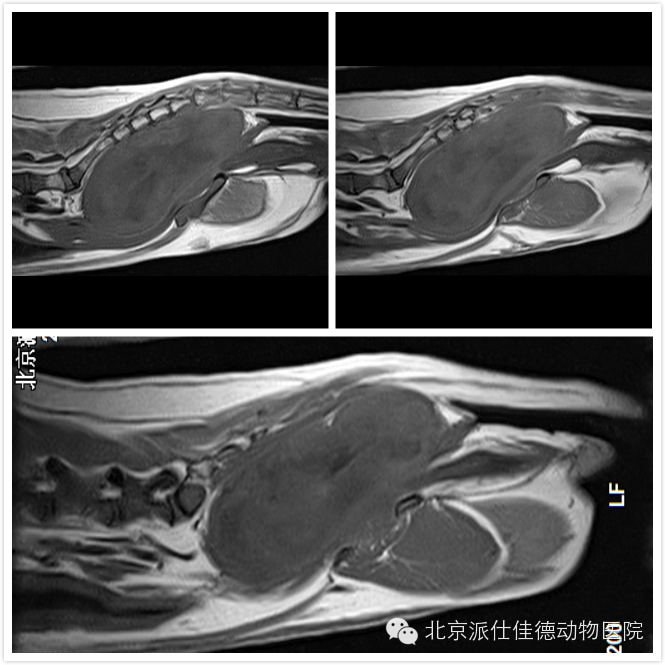

1.有些动物因为视力不好,按照是神经炎治疗,结果通过检查发现是脑肿瘤压迫视神经导致;

7.有些动物表现腰疼,一直按椎间盘突出治疗,结果经诊断为脊椎肿瘤或是椎管内肿瘤或是脊髓本身肿瘤引发。